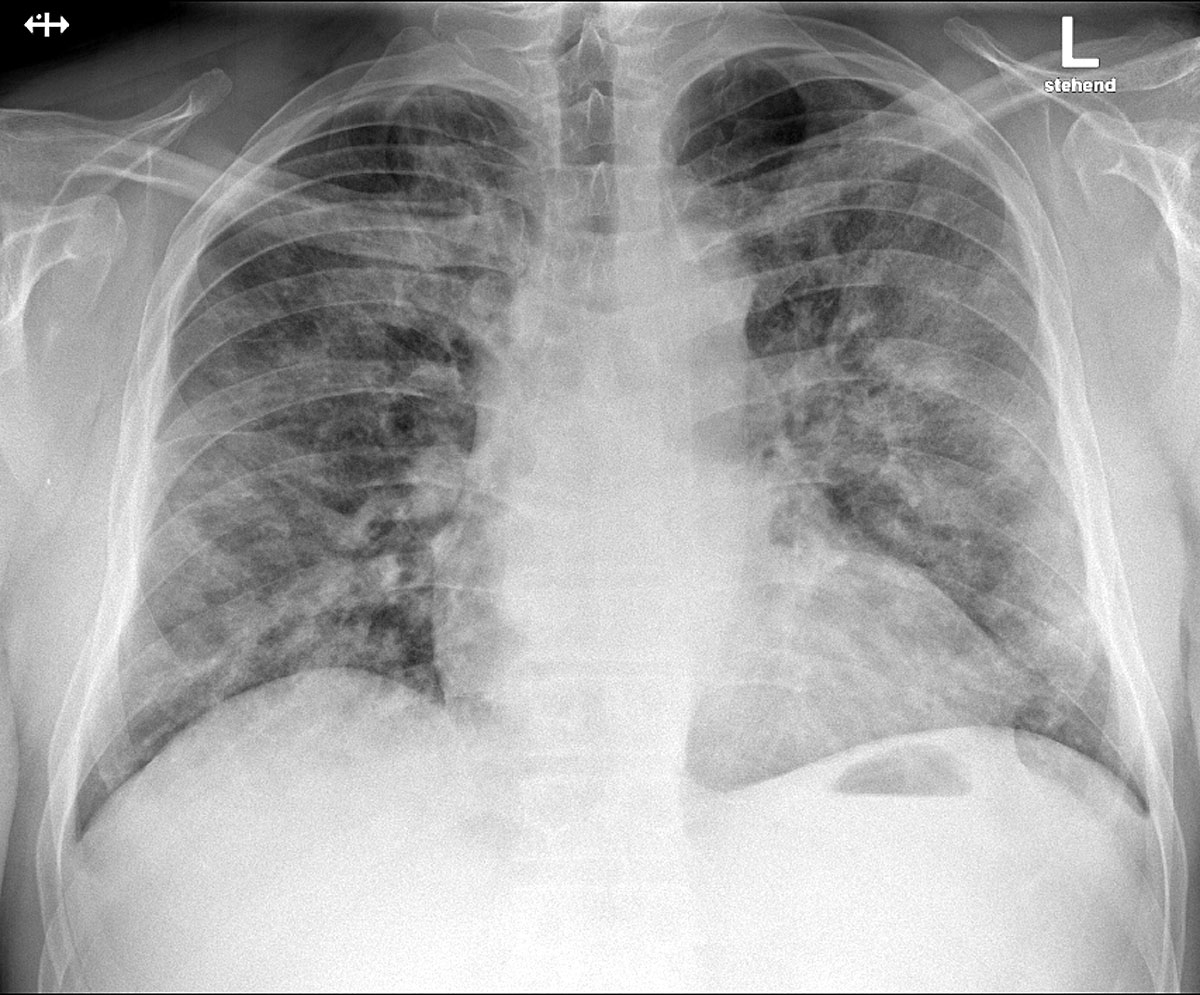

A chest radiograph was performed in the emergency department which demonstrated bilateral patchy perihilar opacities consistent with a pneumonic infiltration, with no evidence of pleural effusions or cardiomegaly (fig. 1). Arterial blood gas measurements revealed type 1 respiratory failure with a compensated respiratory alkalosis on room air (pH 7.44, pCO2 34.5 mm Hg, pO2 72.6 mm Hg, bicarbonate 22.9 mmol/l, base excess −0.7 mmol/l). Full blood count showed no anaemia (haemoglobin 142 g/l), but a slight lymphopenia (leucocytes 4.5 ×109/l, lymphocytes 1.0 ×109/l). Thrombocyte count was normal (194 ×109/L). A chemistry panel showed a raised C-reactive protein (CRP) of 52 mg/l and lactate dehydrogenase (LDH) of 260 U/l with no other significant abnormalities. A nasopharyngeal swab was taken on admission (in keeping with national guidelines recommending testing of all inpatients with suspected respiratory infection) and reported positive for SARS-CoV-2 by RT-PCR. In the initial phase of hospitalisation CRP rose to a peak of 233.4 mg/l on day 5, with ferritin peaking at 2125 µg/l on day 6. Serial measurements of the transaminases peaked on day 5 with an aspartate aminotransferase (ASAT) of 134 U/l and alanine aminotransferase (ALAT) of 119 U/l, and sank below twice the upper limit of normal by day 10. Following the emergence of literature [5] observing a prognostic association, on day 5 we assayed D-dimer, which was elevated (1.33 mg/l).

Figure 1 Posteroanterior chest X-ray at admission, demonstrating bilateral patchy perihilar opacities consistent with a pneumonic infiltration.